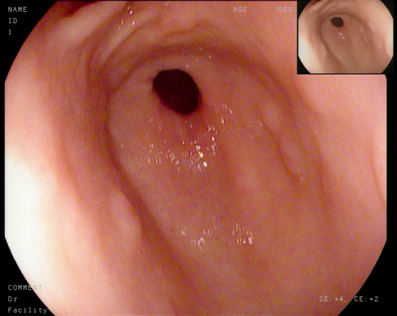

左边是看不到胆汁的胃,右边是能看到胆汁的胃,其实粘膜炎症并没有明显区别